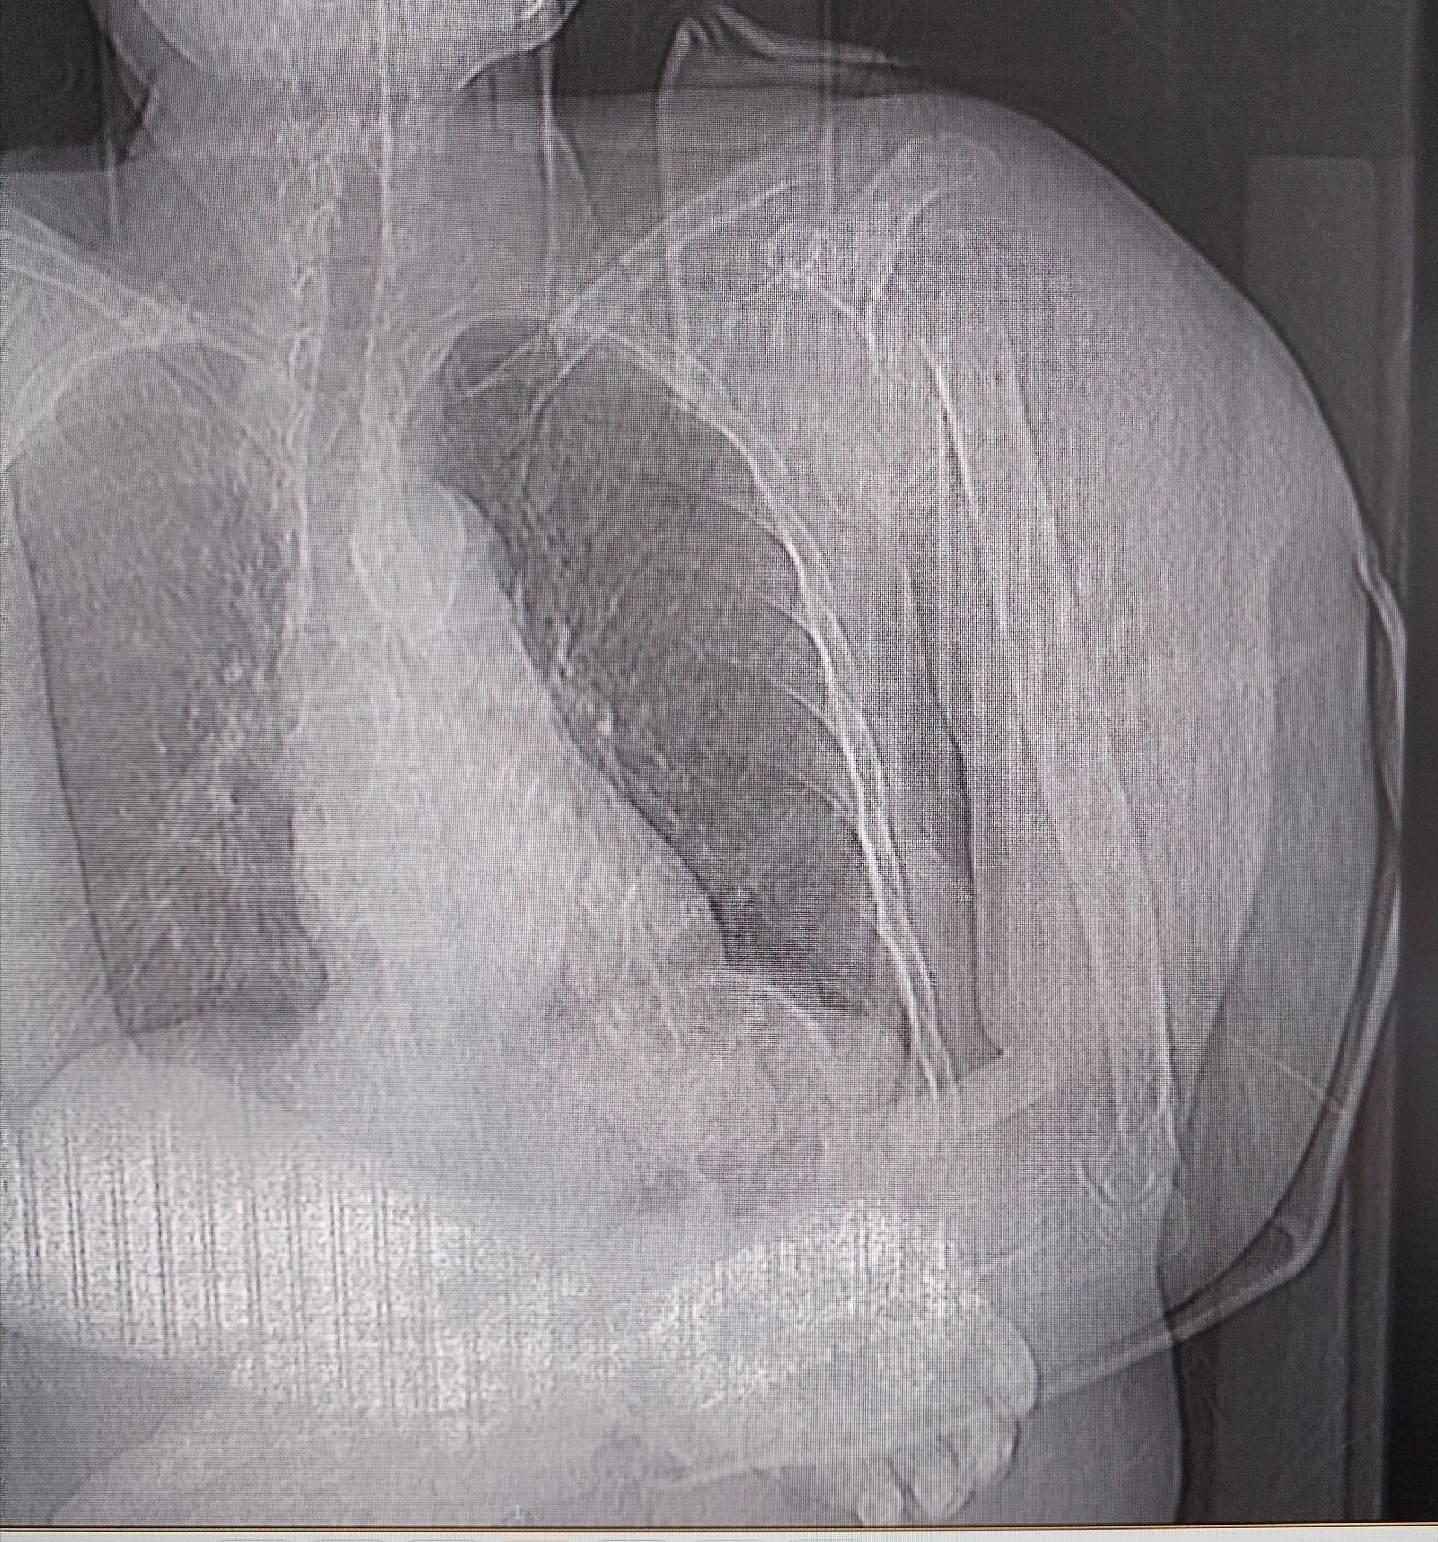

半肩关节置换,肱骨头置换。对于老年人肱骨头粉碎性骨折,肱骨头置换不失为一种合适的选择,完整地重建肩袖是防止术后脱位的关键。